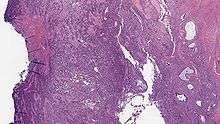

| Micrograph of a low-grade endometrial stromal sarcoma. H&E stain. | |

Low-grade endometrial stromal sarcoma consists of cells resembling normal proliferative phase endometrium, but with infiltration or vascular invasion. These behave more aggressively, sometimes metastasizing, with cancer stage the best predictor of survival. The cells express estrogen/progesterone-receptors.

- Monotonous ovoid cells to spindly cells with minimal cytoplasm.

- Prominent arterioles. Angiolymphatic invasion common.

- Up to 10-15 mitotic figures per 10 HPF in most active areas.

- Tongue-like infiltration between muscle bundles of myometrium.

- May exhibit myxoid, epithelioid and fibrous change.

- May have foam cells or hyalinization in the stroma.